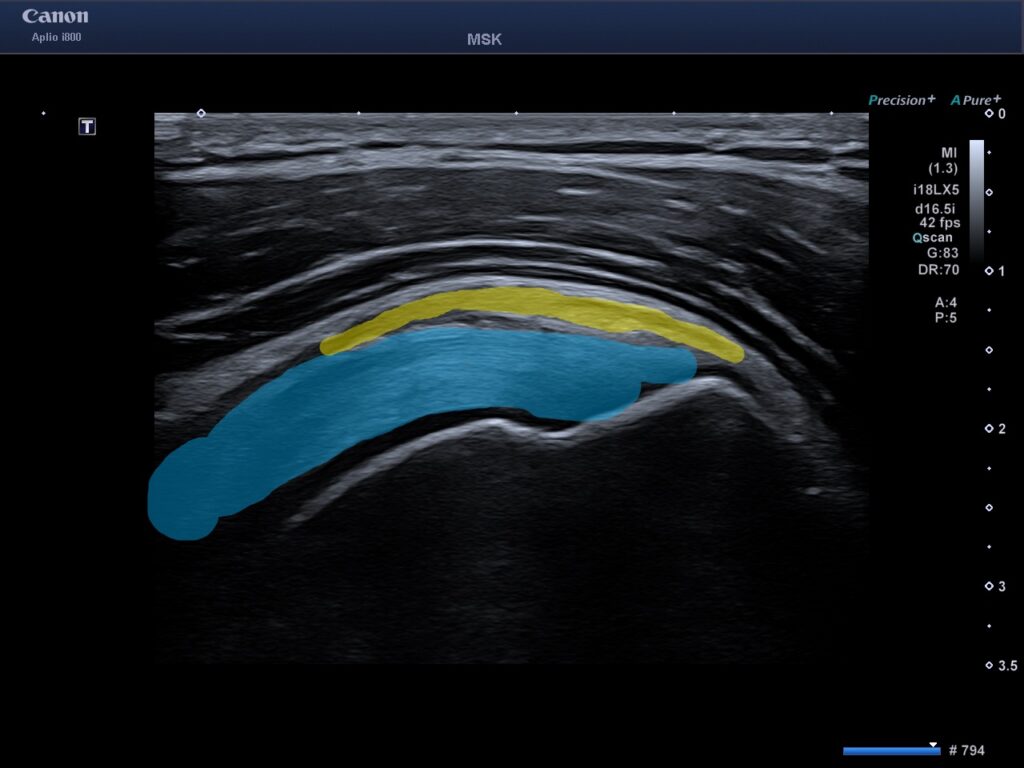

Att undersöka axeln med ultraljud är ofta det mest effektiva sättet att ställa en diagnos vid mjukdelsskador. Till skillnad från en vanlig röntgen ser vi senor, muskler, ligament och slemsäckar i realtid.

- Senskador (Rotatorcuffen): Vi ser om det finns delvisa eller totala bristningar (rupturer) i axelns viktiga senor som supraspinatus, infraspinatus och subscapularis.

- Slemsäcksinflammation (Bursit): Vi mäter vätskeansamlingar och förtjockningar i slemsäcken (subakromiella bursa).

- Impingement (Inklämning): Genom en dynamisk undersökning ser vi vad som händer i axeln när du lyfter armen.

När du kommer till oss i Göteborg börjar vi med en klinisk undersökning där vi testar din rörlighet och styrka. Därefter appliceras en gel på axeln och vi för ultraljudssonden över området. Bilderna visas direkt på en skärm där din behandlare förklarar vad som syns.